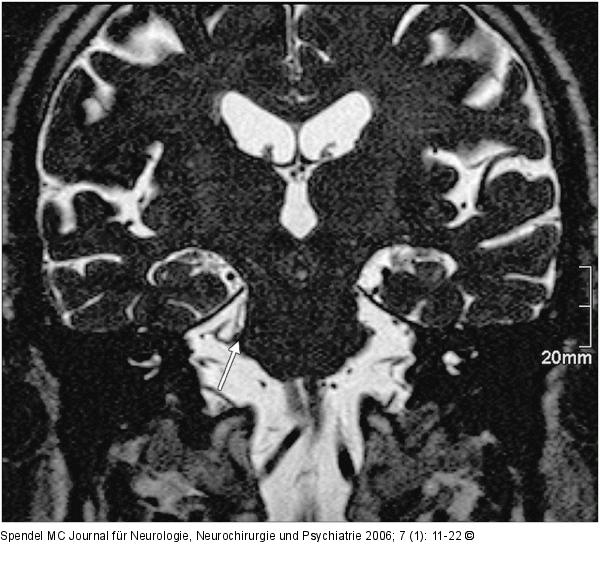

Abbildung 2: Nervus trigeminus - Arteria cerebelli superior Der Pfeil markiert den Nervus trigeminus rechts im Bereich der Eintrittszone im Hirnstamm. Kranial und lateral wird der Nerv von einer Gefäßschlinge der Arteria cerebelli superior komprimiert. |

Der Pfeil markiert den Nervus trigeminus rechts im Bereich der Eintrittszone im Hirnstamm. Kranial und lateral wird der Nerv von einer Gefäßschlinge der Arteria cerebelli superior komprimiert. |